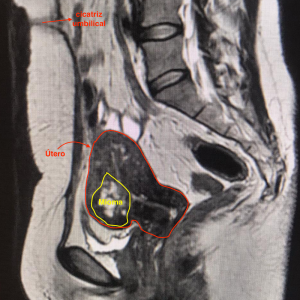

Ressonância magnética após embolização uterina demonstrando importante redução das dimensões do útero e do mioma